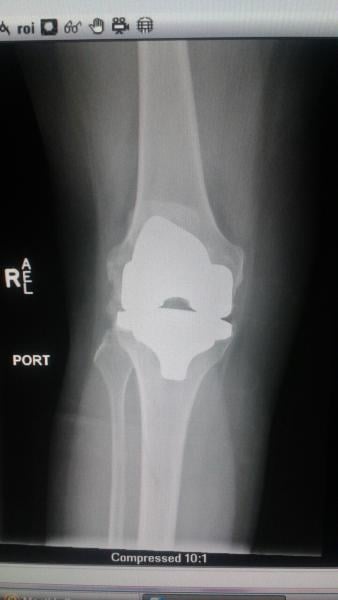

Figure 1. A bedside screen shot of a Carestream DRX mobile X-ray in the ED of the fractured fibula.

Compounding her mobility issues was the fact that she has bilateral knee replacements. (Figure 2) Due to the trauma, broken bone and knowing she had these implants that further limited her ability to move around, she was prescribed a prophylactic anticoagulant.